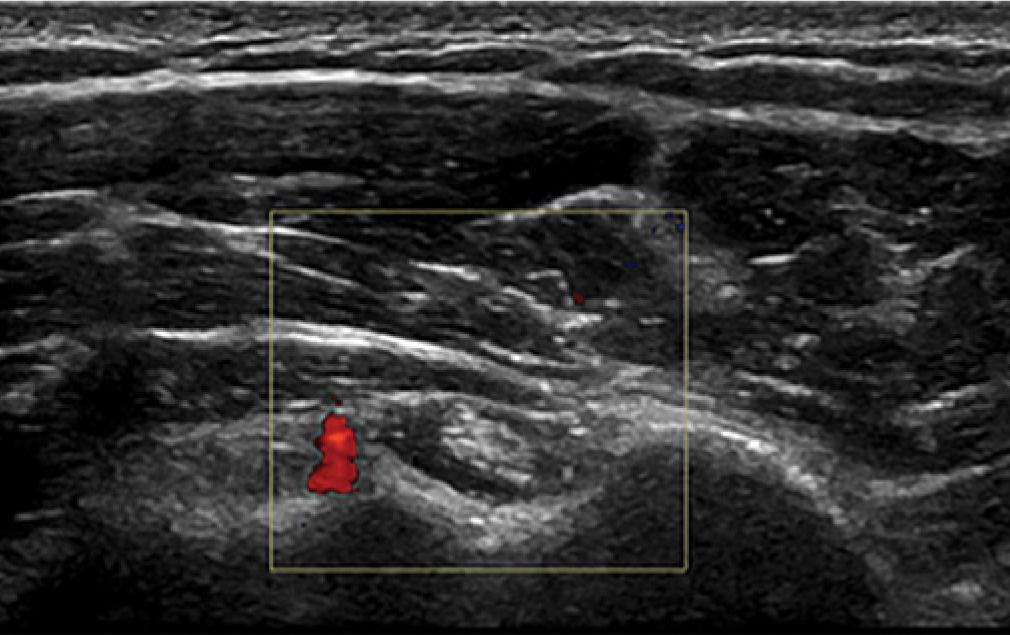

Often this diagnosis is obvious as the patient cannot externally rotate the shoulder for visualization of the subscapularis tendon. There is often a small amount of fluid in the long head of biceps tendon sheath which reflects the small glenohumeral joint effusion that is present (Fig. 7 and Fig. 8).

Fluid in the long head of biceps tendon sheath and the subdeltoid subacromial bursa – transverse view. There is a vessel visible (a branch of the anterior humeral circumflex artery) but no neovascularization

Fluid in the long head of biceps tendon sheath and the subdeltoid subacromial bursa – longitudinal view

Some authors have suggested that the presence of neovascularization in the anterior interval of the rotator cuff or thickening of the coracohumeral ligament can be helpful in establishing the diagnosis of capsulitis(9,10). In my experience, neither of these are necessary or useful and neovascularization within the anterior interval is rare. Some authors suggest looking at the axillary recess(11). This is incredibly difficult in these patients due to the presence of the lack of motion of the shoulder, and in the early phases of severe pain I would not recommend this technique. If the patient has any limitation of external rotation compared to the asymptomatic other shoulder, even if there is no glenohumeral joint effusion or other signs, it is worth treating as capsulitis and they will often benefit.